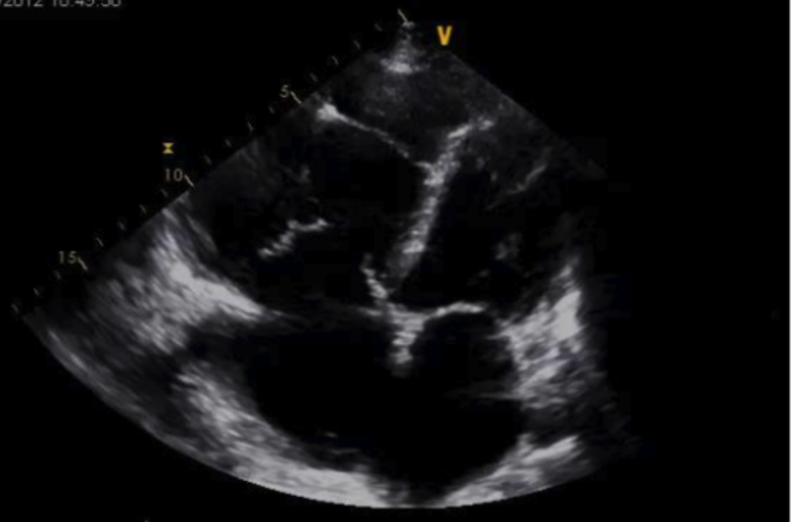

Apical Four Chamber

What am I Looking at?

In A4C view, you can assess LV wall motion at the basal, mid, and apical levels of the inferoseptal and anterolateral walls (figure 19). This view is also useful for visual estimation of overall contractility and evaluation of the LV’s size and shape throughout systole and diastole.

It is important to avoid foreshortening in the A4C view, as this can underestimate LV length and overestimate function. If the LV appears round or blunt at the apex, the image is likely foreshortened—slide the probe laterally and slightly inferiorly to better align with the cardiac apex, and angle it more anteriorly (toward the face) to bring the true apex into view and ensure a full-length chamber.

What is NOT Normal

Decreased global function:

LVfx is considered reduced if the visible walls fail to contract effectively toward the center of the cavity during systole. Wall motion appears sluggish or diminished, and the overall inward movement and thickening are reduced.

Figure 22. A4C view in a child with severe, globally reduced systolic function